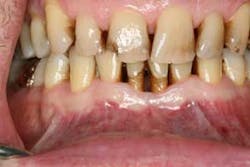

Figures 2a and 2b: Initial presentation in 2011 of the upper right and left molar area, showing advanced bone loss with furcation involvement on the molars.

At presentation, Martin was in his fifties with a medical history significant for controlled hypertension with no known food or drug allergies. He had been lackadaisical with his dental care in the past because of his busy schedule, but he was motivated to get his hygiene and treatment under control. He denied a history of smoking/alcohol/drug use. Based on his full-mouth series (figure 1) and clinical presentation, Martin had generalized, moderate bone loss with localized, severe bone loss in the posterior maxillary right and left quadrants (figures 2a and 2b) as well as the mandibular anterior incisor area (figure 3).